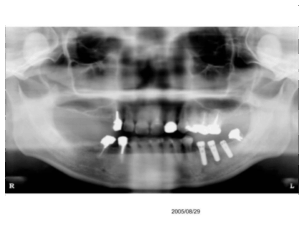

下のレントゲン写真は、左下の奥歯にインプラントを埋入し、骨との結合を待っている間のものです。今から約20年前のレントゲン写真です。

この状態では、右側のごく一部の歯と前歯でしか噛むことができません。(レントゲン写真は左右反転されているため、向かって左側です)

したがって、下のレントゲンの赤丸で囲まれた神経を抜いてある歯は、クラスプをかければ数年で抜歯となることが予想されました。また、左下(向かって右)は右よりはましですが、同様に抜歯となっていた可能性が高かったのです。